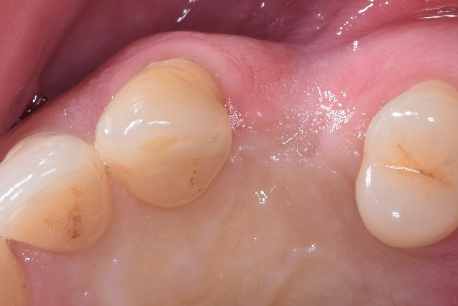

După perioada de osteointegrare a implantului acesta se descoperă, adică se creează o cale de comunicare cu mediul bucal, el până în această etapă fiind acoperit de gingie. Se instalează apoi un bont de vindecare care are rolul să ghideze vindecarea gingiei în jurul implantului.(Fig. 3.5.5 și 3.5.6) Cu acest bont pacientul așteaptă o perioadă variabilă de 14-21 de zile, iar dacă după acest interval gingia este vindecată, se poate trece la etapa următoare – cea de amprentare.